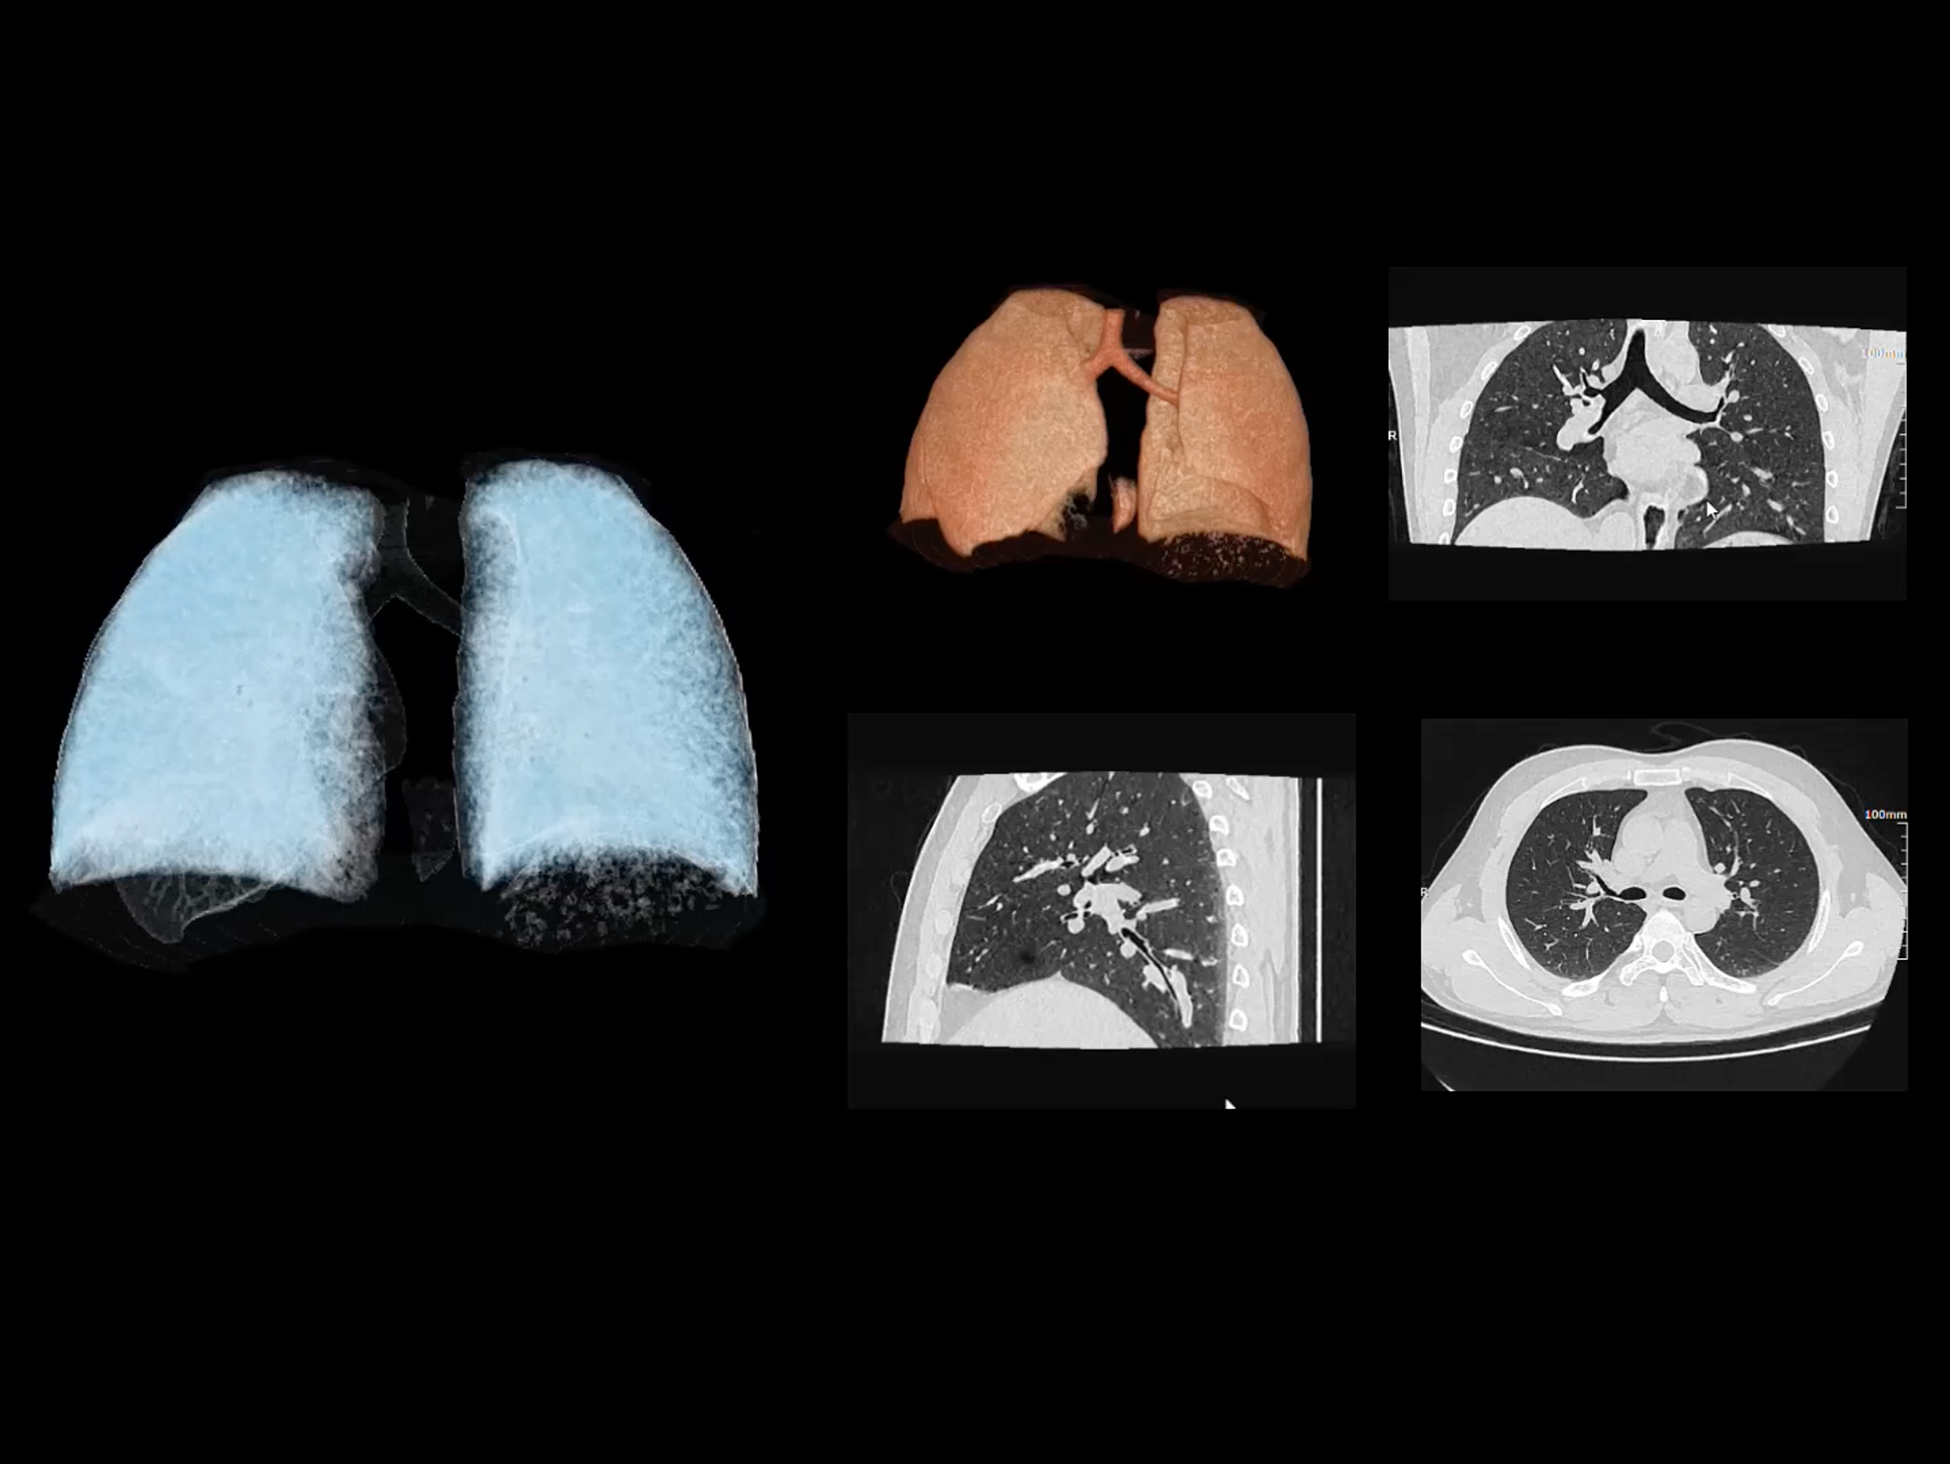

全身运动

uCT SiriuX® 以全新双宽体系统架构,同步实现超高时间分辨率与宽体容积覆盖兼得,全面释放性能潜能,敏锐捕捉人体生理运动全景,带来动态影像新视角。

巅峰系统形态

双宽体“零”噪声时空探测器,Z 方向覆盖达16 cm,单圈即可完整扫描头颅、心脏等关键器官,结合超高时间分辨率,可实现真正意义上的全身各部位高清动态成像,让每一次扫描都更高效、更精准。

全身各部位动态CT成像